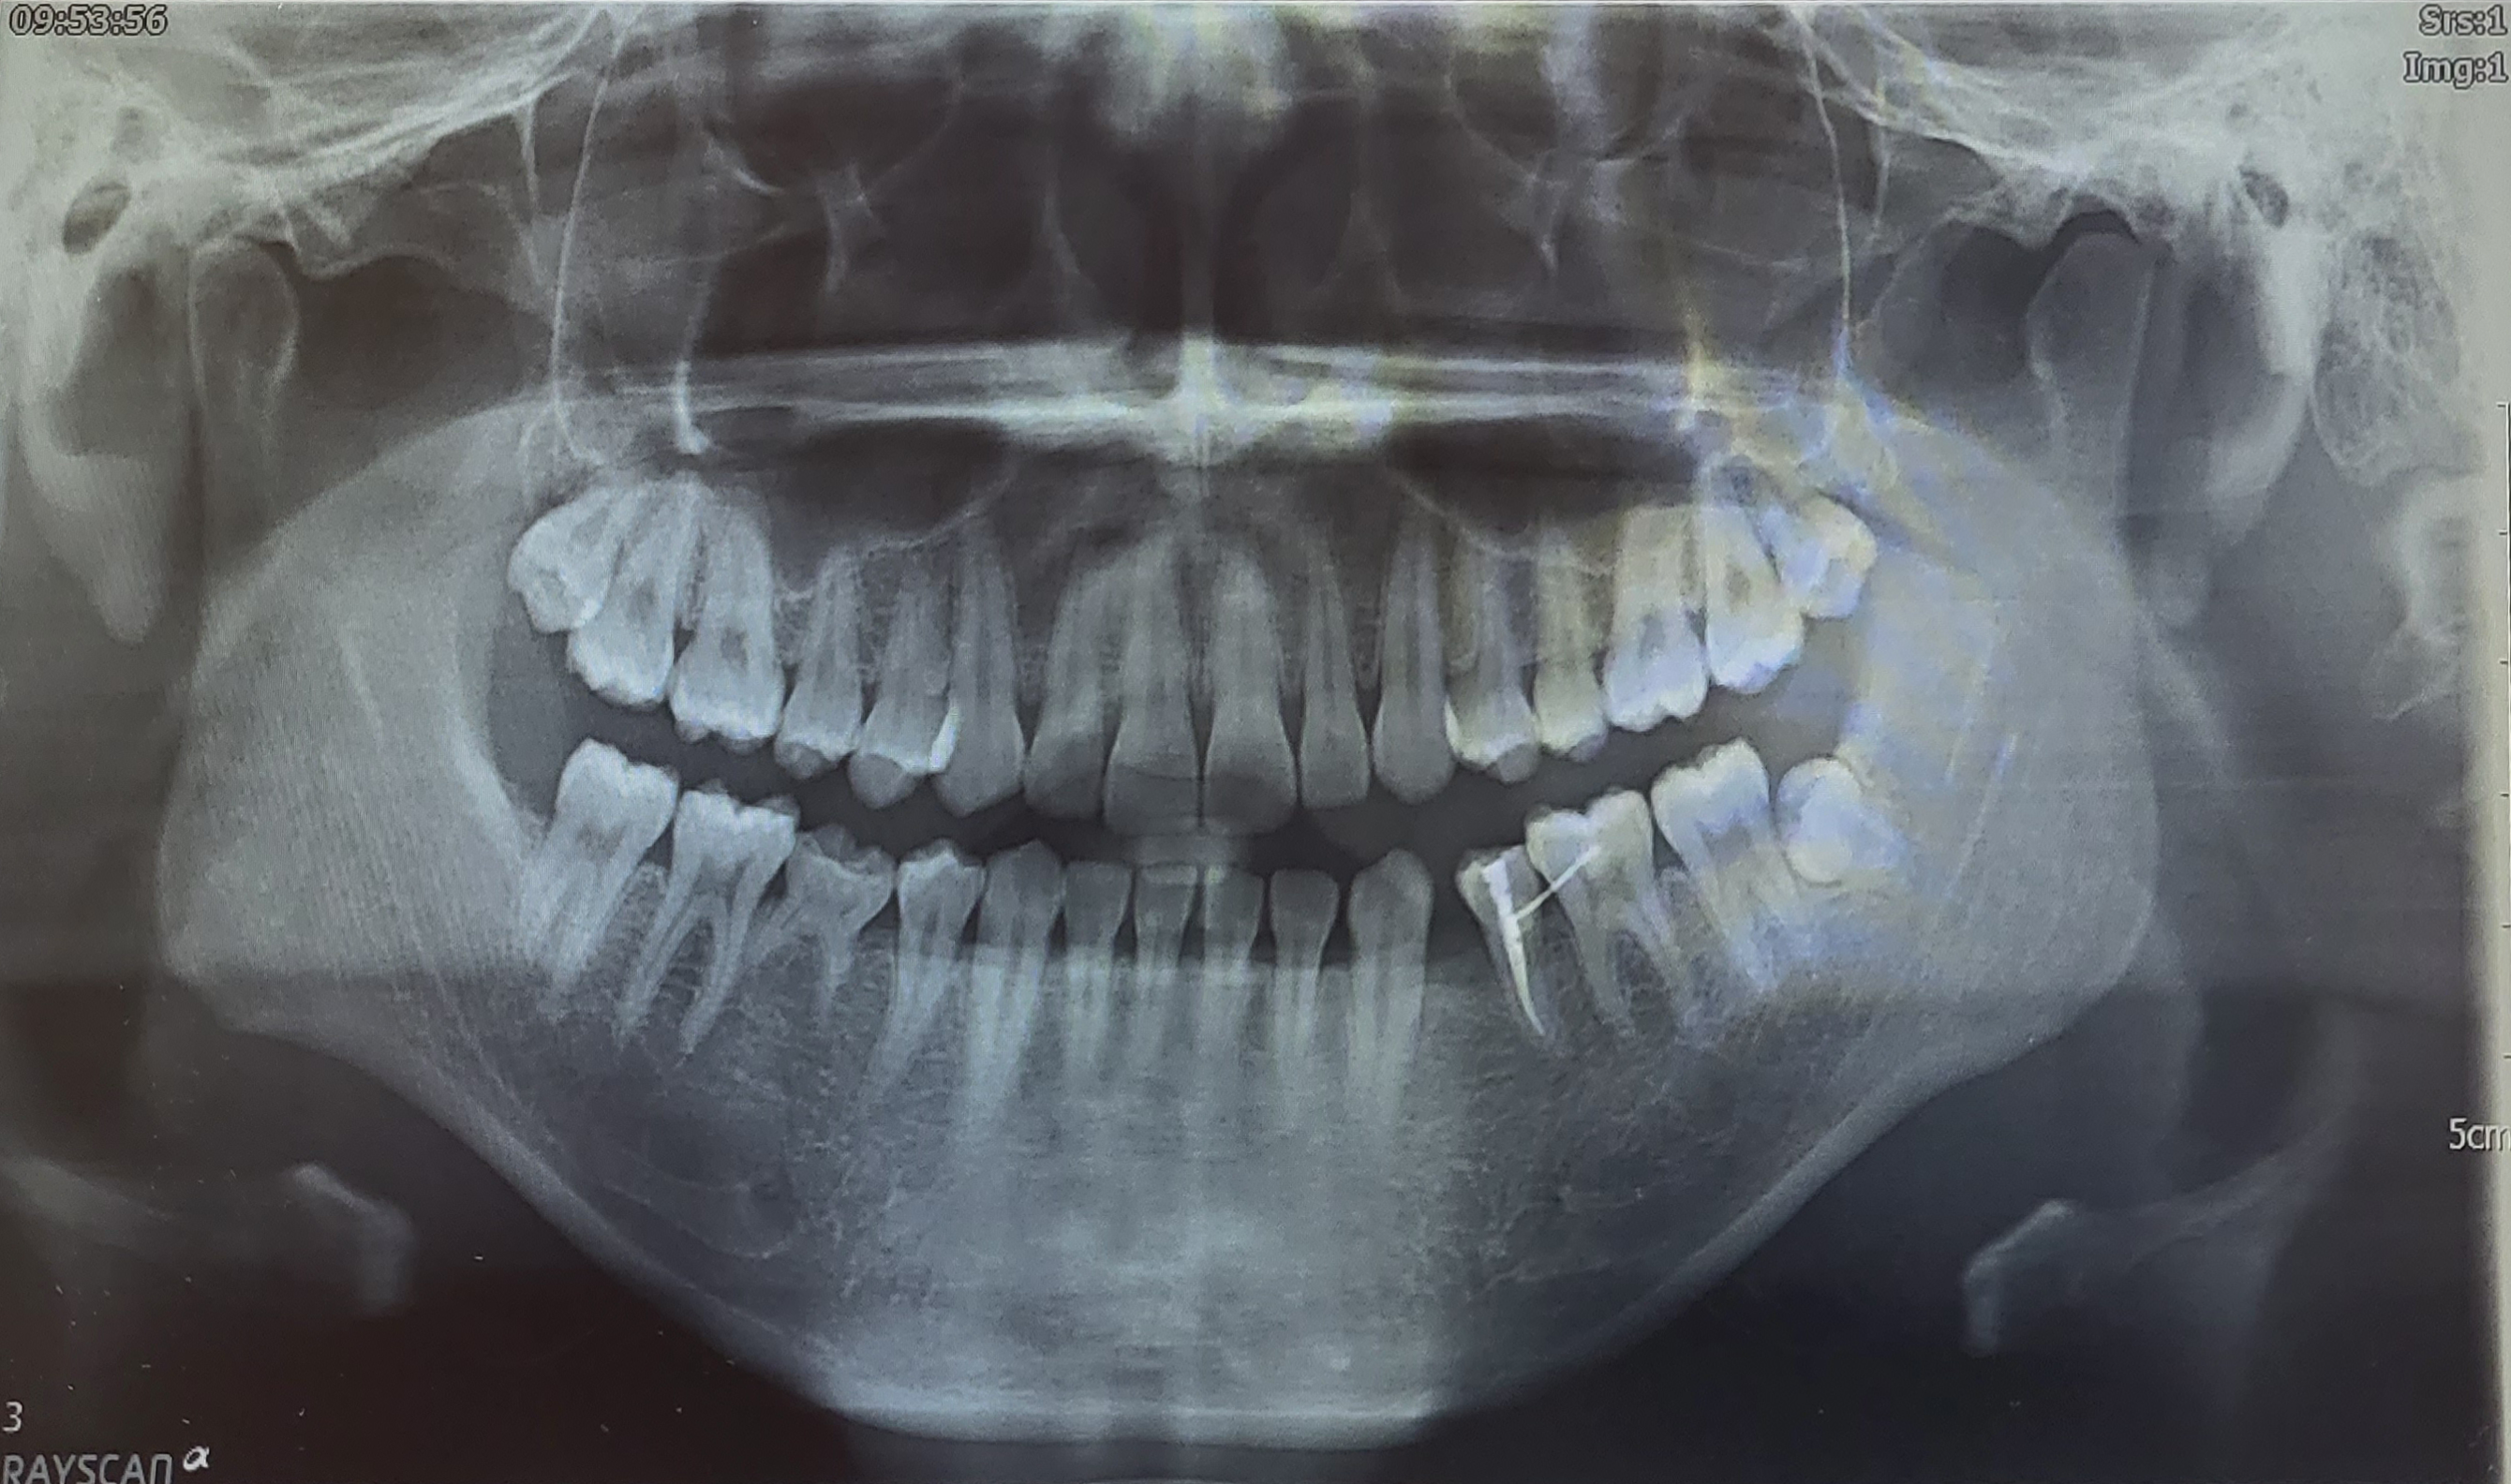

본인은 선천적으로 하악(아래턱)의 어금니 2개가 영구치가 없다. 의학적으로 정확한 용어인지는 모르겠지만 본인 기준의 하악 좌측 작은 어금니(제1소구치)와 하악 우측의 어금니(제2소구치)가 영구치가 없다. 오른쪽 턱의 제2소구치 유치는 튼튼하게 자리 잡고 있지만 왼쪽 제1소구치는 빠져버린 상태다.

2번째 치과에서는 임시로 씌워놨던 레진을 제거하고 나서는 아랫니가 빠진 빈자리에 예전처럼 탈착식 공간 유지장치를 하지 않았다. 그 대신 옆 어금니 2개에 와이어를 부착해 치아가 쓰러지지 않도록 했다. 다시 말해 왼쪽 제2소구치와 제1대구치에 와이어를 부착했다. 추가적으로 무너졌다가 다시 일으키느라 뿌리가 드러나고 아팠던 옆의 이(왼쪽 제2소구치)는 신경치료를 하게 되었다. 사실 이 당시에는 내가 받았던 시술이 신경치료인지 전혀 알지도 못하는 상태에서 받았다...^^;